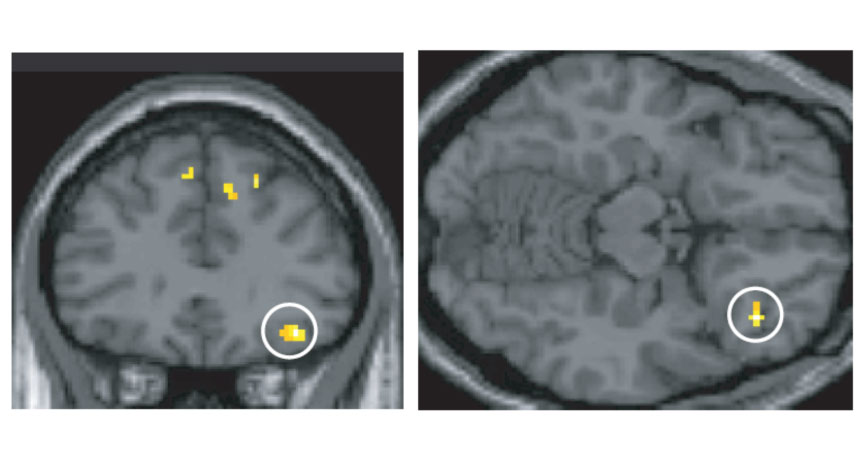

BRAIN BRIDGE The right orbitofrontal cortex (circled in two different views of the brain) is one of two brain regions that serve as an interface between odor and language networks, new experiments show.

A separate group of people then underwent similar experiments in an fMRI machine, which allowed the researchers to pinpoint the two areas of the brain that seemed to be deciding what each smell was. These regions, the anterior temporal lobe and orbitofrontal cortex, are both closely connected to the olfactory cortex, the brain’s primary headquarters for smell information. The findings suggest that these regions are talking to brain areas directly involved in language.